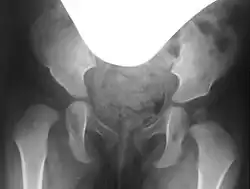

Bei der Hüftdysplasie fehlt dem Hüftkopf die seitliche (laterale) und vordere (ventrale) Überdachung (auch Pfannenerker genannt). Der „zukünftige“ Hüftkopf wird nicht korrekt überdacht und droht – je nach Schweregrad der Dysplasie – nach oben abzurutschen und zu luxieren (auszurenken).[1]

Präoperativ werden sowohl zur genauen Beurteilung der Gelenkfehlstellung und des Schweregrades als auch zur Planung der Operation selbst konventionelle Röntgenbilder des Beckens, sogenannte Beckenübersichtsaufnahmen und Rippstein-Aufnahmen, angefertigt. Die Rippstein-Aufnahmen dienen der genaueren Beurteilung der Schenkelhälse in einer seitlichen Projektion.[4][5]